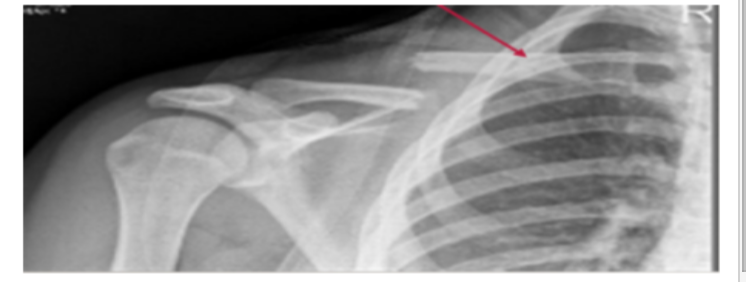

Clinical:

What happens when the Clavicle is fractured?

A

1. Medial end is pulled up by SCM (sternocleidomastoid)

2. Lateral end is pulled down by body weight